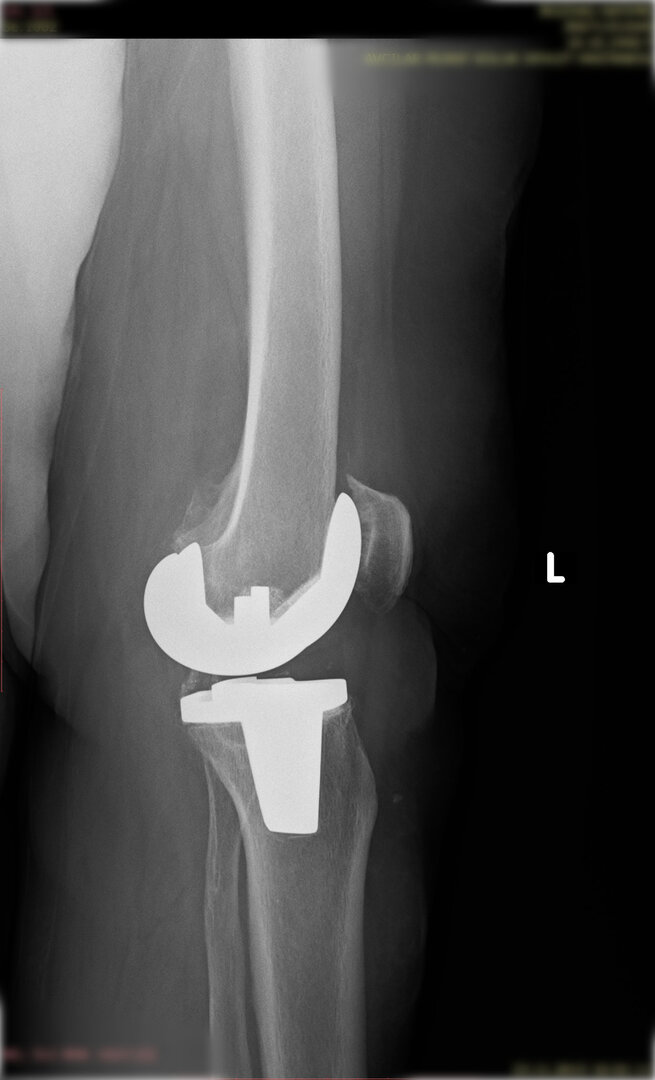

Aşınmış, hasar görmüş ya da eklem yüzeyleri tamamen bozulmuş diz ekleminin, yapay bir eklemle değiştirme işlemidir. Ameliyatta, ağrıya neden olan hasarlı kemik ve kıkırdak dokular çıkarılarak; yerine metal ve özel plastikten yapılmış, uzun ömürlü bir protez yerleştirilir. Bu sayede diz, tekrar ağrısız ve stabil bir şekilde çalışır hale gelir.

Eklem yüzeyleri özel kılavuzlar yardımı ile temizlendikten sonra metal protez eklem yüzeylerine bir kemik çimentosu ile adapte diyoruz. Bu iki metal yüzeyin sürtünmesini azaltmak için polietilenden yapılmış özel bir plastik tabakayı sisteme dahil ediyoruz.